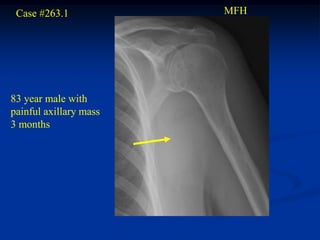

Case #263.1            MFH

83 year male with

painful axillary mass

3 months

CT scan